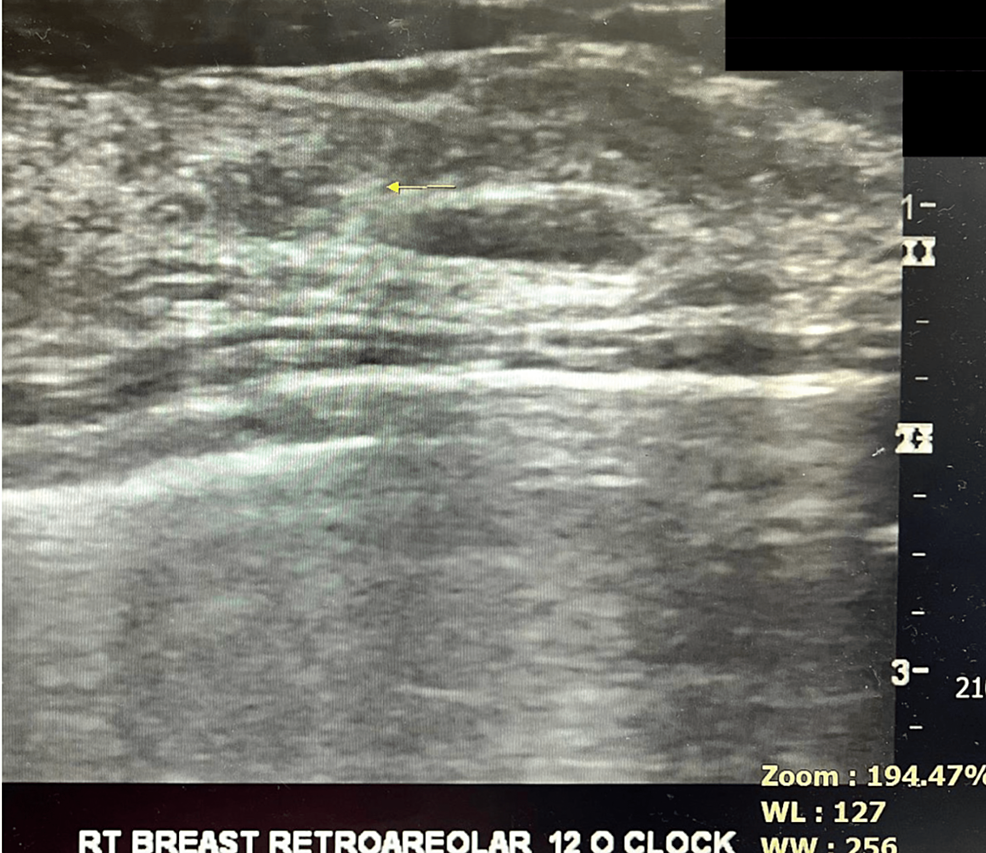

From www.cureus.com

Cureus Ultrasound Guided Intraoperative Wire Localization Under Putting A Wire In Breast Before Surgery for decades, wire localization has been the standard for preoperative localization in breast imaging. you may have a wire guided localisation before your surgery. • a wire localization is done by radiology to help your surgeon to locate the area of breast t issue that needs to be removed. This is done to assist the surgeon to. Putting A Wire In Breast Before Surgery.